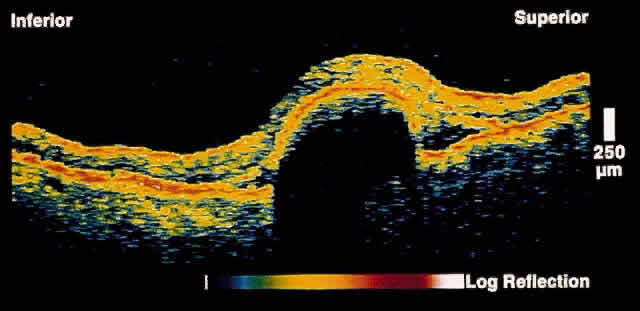

and reliable method to distinguish the two entities.17 In retinoschisis, OCT images show splitting of the neurosensory retina

consistent with the known histopathology of a separation at the outer

plexiform layer (Fig. 14). Retinal detachment presents as a separation of full-thickness neural

retina from the underlying RPE band (Fig. 15). Although lesions anterior to the equator cannot be imaged by OCT, most

lesions that are posterior to the equator, or that have a component

posterior to the equator, can be effectively imaged.  Fig. 14. OCT image through peripheral retinal elevation suspected to be retinoschisis versus retinal detachment. This image shows a splitting of the neurosensory retina

consistent with retinoschisis. Fig. 14. OCT image through peripheral retinal elevation suspected to be retinoschisis versus retinal detachment. This image shows a splitting of the neurosensory retina

consistent with retinoschisis.

Fig. 15. OCT image through peripheral retinal elevation suspected to be retinoschisis versus retinal detachment. This image shows a full-thickness detachment of the

neurosensory retina consistent with a retinal detachment. In contrast

to retinoschisis, splitting of the neurosensory retina is not present. Fig. 15. OCT image through peripheral retinal elevation suspected to be retinoschisis versus retinal detachment. This image shows a full-thickness detachment of the

neurosensory retina consistent with a retinal detachment. In contrast

to retinoschisis, splitting of the neurosensory retina is not present.